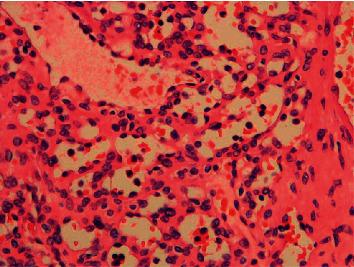

Anastomosing haemangioma is a rare benign vascular neoplasm, which may mimic angiosarcoma histologically. We here present a case of anastomosing haemangioma arising from the kidney. This patient presented with a large kidney mass and adrenal mass. The clinical and radiological findings were suspicious for renal cell carcinoma with metastasis. Radical nephrectomy and adrenalectomy were thus performed. Histopathological examination and immunohistochemical studies concluded a diagnosis of anastomosing haemangioma of the kidney and concurrent adrenal cortical adenoma. It is important to differentiate this tumor from other borderline or malignant vascular neoplasms.